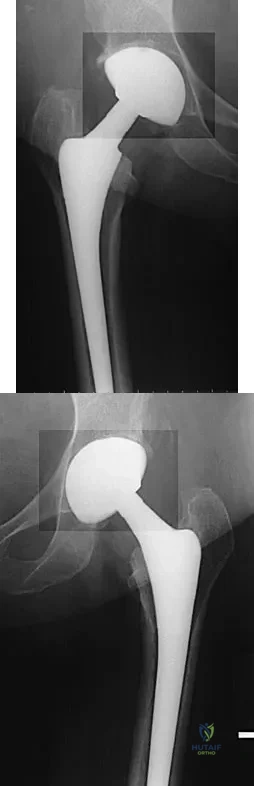

A 68-year-old woman underwent a successful total right hip arthroplasty with a metal-on-metal articulation and cementless porous-coated components. Three months later, she underwent identical surgery on the left hip. Three months after surgery on the left hip, she reports groin pain on ambulation. Examination reveals significant groin discomfort with passive hip motion, particularly at the extremes of motion. Radiographs are shown in Figures 21a and 21b. Laboratory studies show an erythrocyte sedimentation rate of 35 mm/h and a C-reactive protein of 0.9. Aspiration yields scant growth of Staphylococcus epidermidis in the broth only, with no evidence of loosening on arthrography. A second aspiration yields scant growth of Staphylococcus epidermidis in the broth only. What is the most likely cause of the patient's pain?